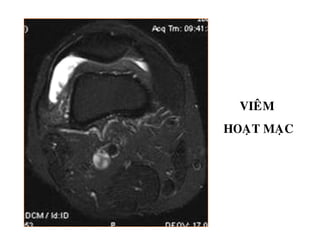

Vieâm hoaït maïc

VIEÂM

HOAÏT MAÏC